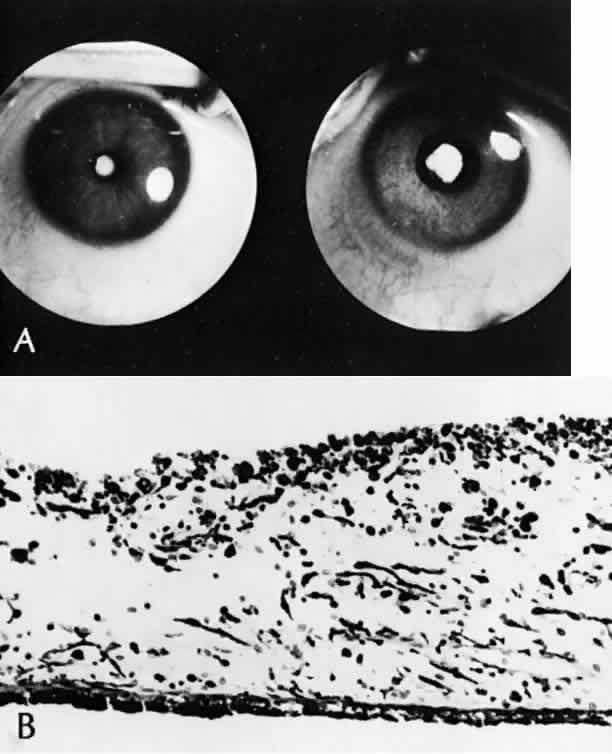

The iris can be leathery and dilates poorly in response to mydriatics. Histologically, the iris has a poorly developed dilator muscle, with necrosis of the iris and ciliary body epithelium and chronic nongranulomatous inflammation of the stroma (Fig. 16).118 This inflammatory reaction sometimes becomes clinically manifest after cataract extraction, which can lead to cyclitic membrane formation and retinal detachment.119

Fig. 16. Rubella. A. Same eye before (left) and after (right) maximal dilatation with mydriatics. A dense nuclear cataract can be seen in the minimally dilated pupil. Iris is leathery and difficult to dilate (SEI 73–631). (Courtesy of Dr. HG Scheie) B. Iris is atrophic, is infiltrated with plasma cells and lymphocytes (chronic nongranulomatous iritis), and shows a loss of the dilator muscle (H&E, × 130 [SEI 79-36]). (Yanoff M, Schaffer DB, Scheie HG: Rubella ocular syndrome: Clinical significance of viral and pathologic studies. Trans Am Acad Ophthalmol Otolaryngol 72:896, 1968)

Probably the most characteristic finding is the “salt-and-pepper” fundus, present in up to 60% of cases.116 Histologically, the retinal pigment epithelium is intact throughout but shows focal areas of hyperpigmentation and hypopigmentation (Fig. 17).118,120 Some older patients have developed subfoveal neovascularization.121,122

Fig. 17. Rubella. A. Fundus picture shows mottled “salt-and-pepper” appearance (SEI 79-37). B through D. All from same eye. Retinal pigment epithelium shows areas of hyperpigmentation (B), hypopigmentation (C), and alternating areas of hypo- and hyperpigmentation (D) (B, C, and D, H&E, × 630 [SEI 79-38, 79-39, and 79-40)]. (Modified from Yanoff M: The retina in rubella. In Tasman W [ed]: Retinal Diseases in Children, p 223. New York, Harper & Row, 1971.